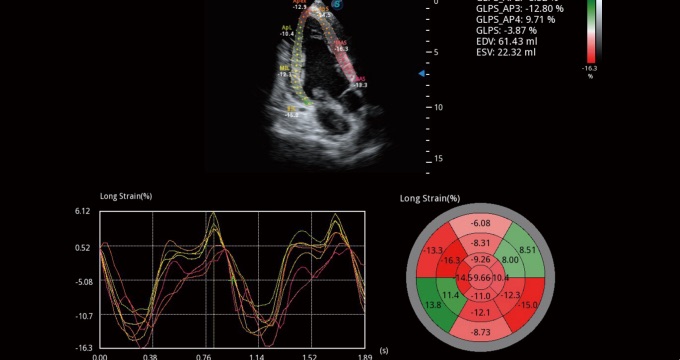

• 心肌定量分析 MQA

通过心肌识别技术和二维斑点追踪技术相结合,计算心肌各节段的应变、应变率、速度、位移并以曲线图显示,实现整体或者局部心肌定量分析。同时牛眼图可更直观和准确诊断心肌的运动情况。